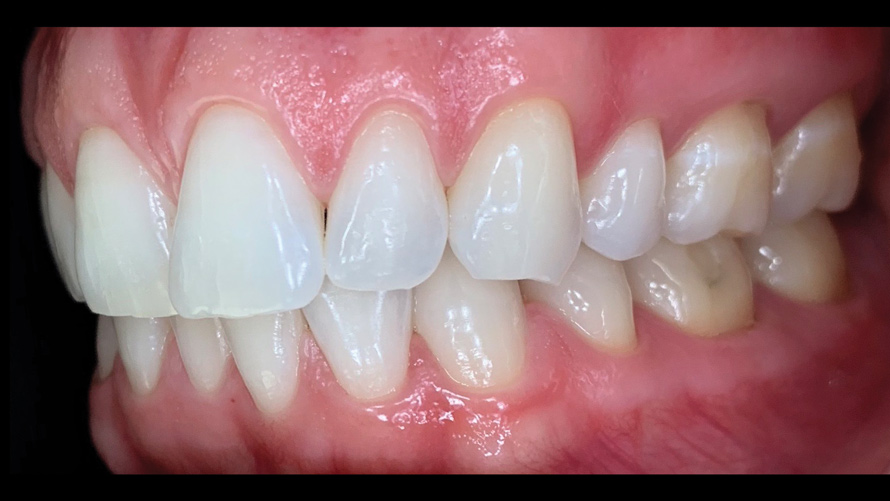

(18. and 19.) Tooth shade analysis of value, chroma, and hue taken with a smartphone and an EALS device.

Figure 18

Figure 19

Shade Selection and Laboratory Communication

The most utilized intraoral photographs in the field of dentistry are perhaps those that capture shade information (Figure 18 and Figure 19). The analysis of color (ie, value, chroma, hue) in dentistry is a critical step in the fabrication of esthetic indirect restorations, such as all-ceramic crowns and porcelain laminate veneers. The ability to properly communicate this information with the dental laboratory is essential to ensure an appropriate shade match, a reduction in chairtime and overhead, and most importantly, a satisfactory patient experience and treatment outcome. In recent years, the use of polarized light photography as an aid in the shade selection process has become extremely popular. For some EALS devices, special polarizing filters have been specifically designed to fit over the light-emitting portion of the device (Figure 20 and Figure 21). The images produced using polarized light photography demonstrate an elimination or reduction in the specular reflection of hard and soft tissue, resulting in a matte-finish appearance of the dentition and gingiva. These types of photographs aid the ceramist in identifying areas of opacity and translucency, crack lines, hypo- or hypercalcification, and other internal features of the dentition that may not be readily visible without such a filter (Figure 22).